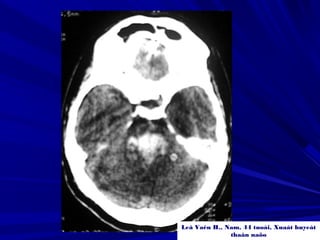

Leâ Vaên H., Nam, 44 tuoåi, Xuaát huyeát

thaân naõo

XUAÁT HUYEÁT THAÂN NAÕOXUAÁT HUYEÁT THAÂN NAÕO